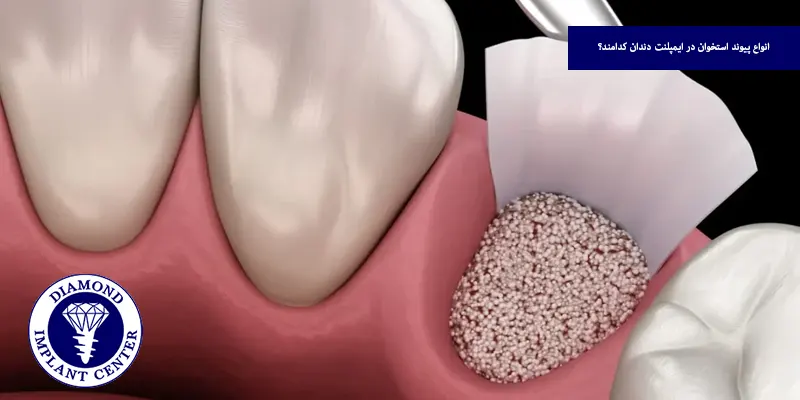

انواع پیوند استخوان در ایمپلنت دندان کدامند؟

پیوند استخوان برای ایمپلنت دندانی به روشهای گوناگونی انجام میشود که انتخاب نوع آن بر اساس وضعیت استخوان فک، هدف درمان، شرایط عمومی بیمار و نظر متخصص صورت میگیرد و هر کدام از این روشها ویژگیها و کاربردهای خاص خود را دارند و ممکن است بسته به شرایط، با یکدیگر ترکیب شوند، در ادامه با مهمترین انواع پیوند استخوان مورد استفاده در درمانهای ایمپلنت آشنا میشویم:

قرار دادن ماده پیوندی

در این مرحله، ماده پیوندی از نوع اتوگرافت، آلوگرافت، زنوگرافت یا مصنوعی با دقت در محل مورد نظر قرار میگیرد، در برخی موارد از غشاهای مخصوص برای پوشاندن پیوند و افزایش پایداری آن استفاده میشود و این غشاها مانع ورود سلولهای ناخواسته به ناحیه پیوند شده و به بازسازی استخوان کمک میکنند.